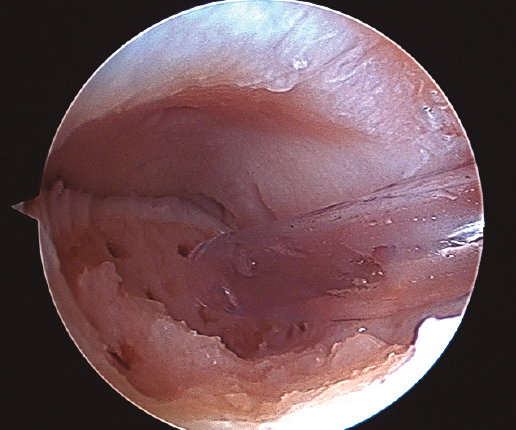

Figura 3. Secado de la articulación con aspirador.

- Una vez se completa el desbridamiento de la capa mineralizada, detenemos la infusión de suero salino y procedemos al secado meticuloso de la misma mediante aspiración y empleo de gasas y torundas (Figura 3).